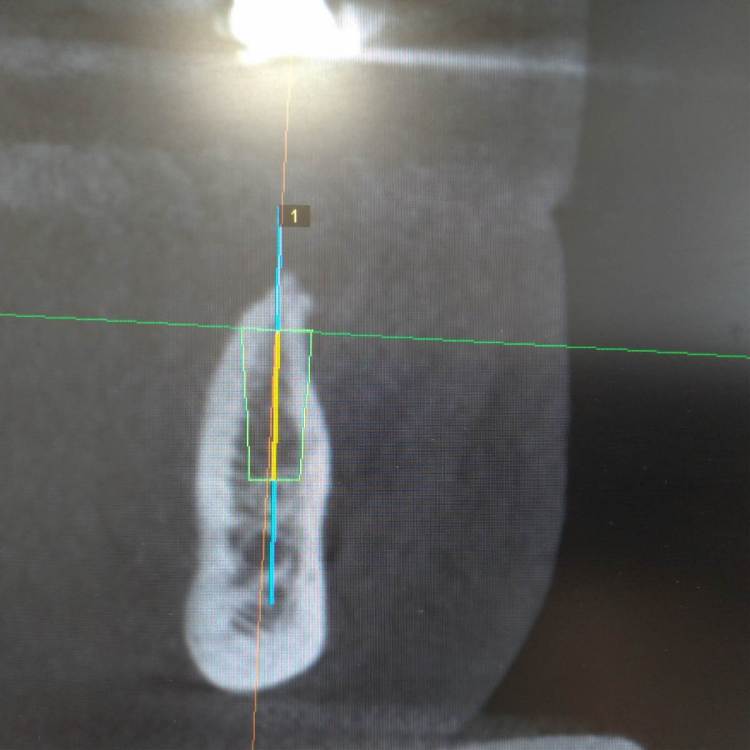

It'sGeorgy Опубликовано 4 апреля, 2022 Поделиться Опубликовано 4 апреля, 2022 Добрый вечер. Есть ощущение, что вас очень широкий винт на планировании. Я бы, в любом случае, взял винт поуже и либо поставил поглубже, либо ТЛ+редукция. Ссылка на комментарий

Macor Опубликовано 12 апреля, 2022 Поделиться Опубликовано 12 апреля, 2022 3.5 взять и поглубже установить,место есть Ссылка на комментарий